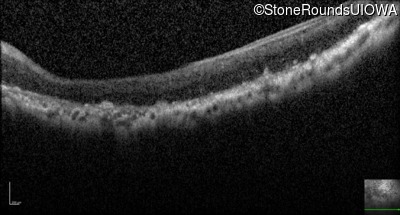

Optical Coherence Tomography - Left - Light Perception

Exemplar